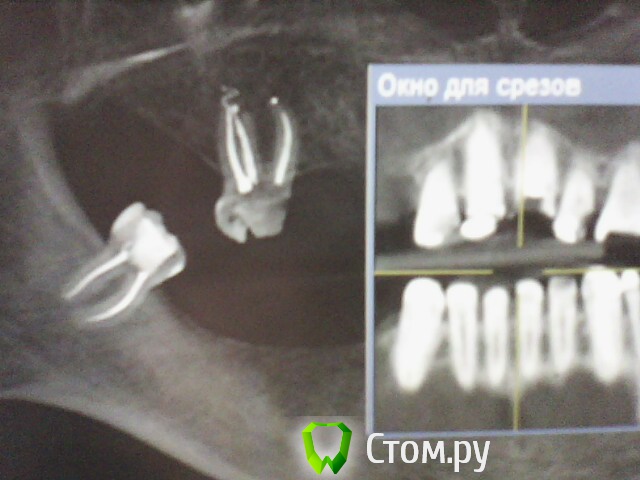

ОльгаS Опубликовано 7 октября, 2014 Поделиться Опубликовано 7 октября, 2014 Рентген показал что в зубом все в порядке, КТ - гранулему и что то там с корнем, если правильно поняла, какое то скрещивание: Ссылка на комментарий